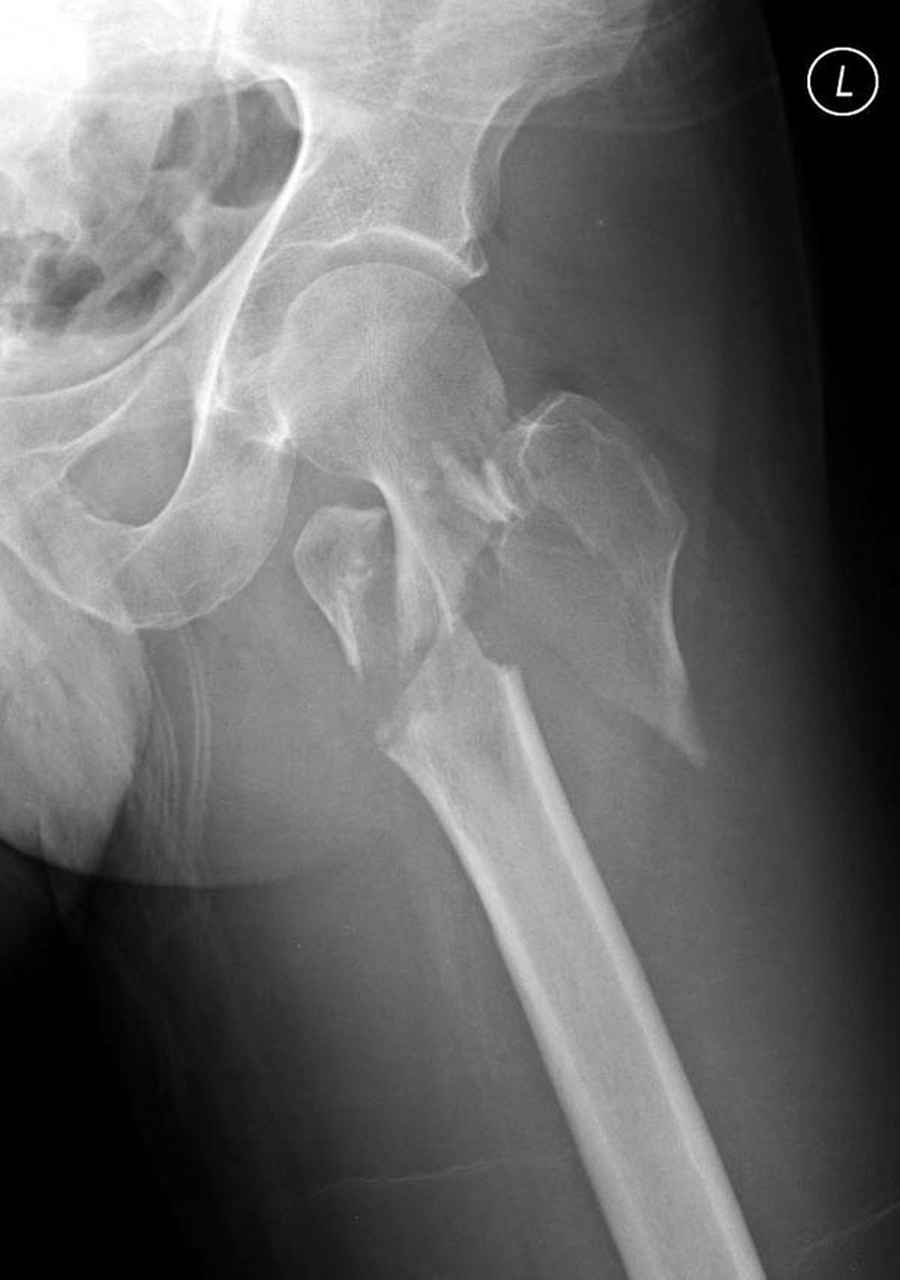

Здесь пара случаев фиксации похожих переломов:

первый высокоэнергетическая травма 36 лет